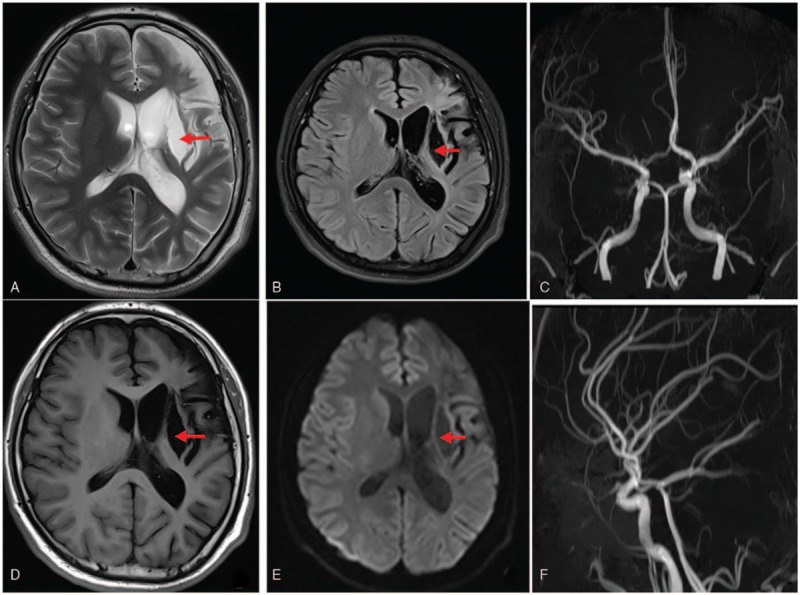

The patient was followed up for 3 years. The patient could take care of his daily routines and studies. He had a clear consciousness, no aphasia, and no obvious abnormalities in the cranial nerve examination. The muscle tensions in the 4 limbs were normal, while the proximal and distal ends of the right upper limb muscle strength, and the muscle strength of the right lower limb was at level 5. The results of blood lipid examinations after 3 years of follow-up are shown in Table 1, and the reexamination of brain MRI and MRA were illustrated in Fig. 5.

Figure 5.

MRI after 3 years of follow-up (A, B, D, E): Long T1 and T2 signals on the left basal ganglia. FLAIR and DWI showed low density and softening lesion and atrophy of the left frontal lobe (red arrow). (C, F) MRA: Intracranial vascular images of the patient were satisfactory without obvious vascular stenosis. DWI = diffusion-weighted imaging, FLARE = fluid-attenuated inversion recovery, MRI = magnetic resonance imaging.